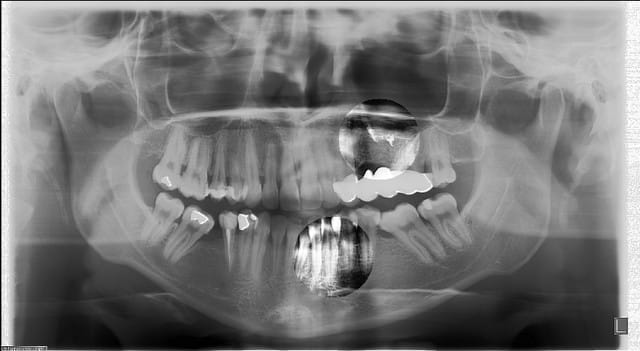

je viens d'acquérir une pano OP100D de General Electric (marque Instrumentarium) c'est ce qu'il se fait de mieux a mon sens aujourdh'ui

je joints une radio d'un patient que je viens de faire (possibilité de faire des zones de renforcement ou on veut voir mieux) A VOIR